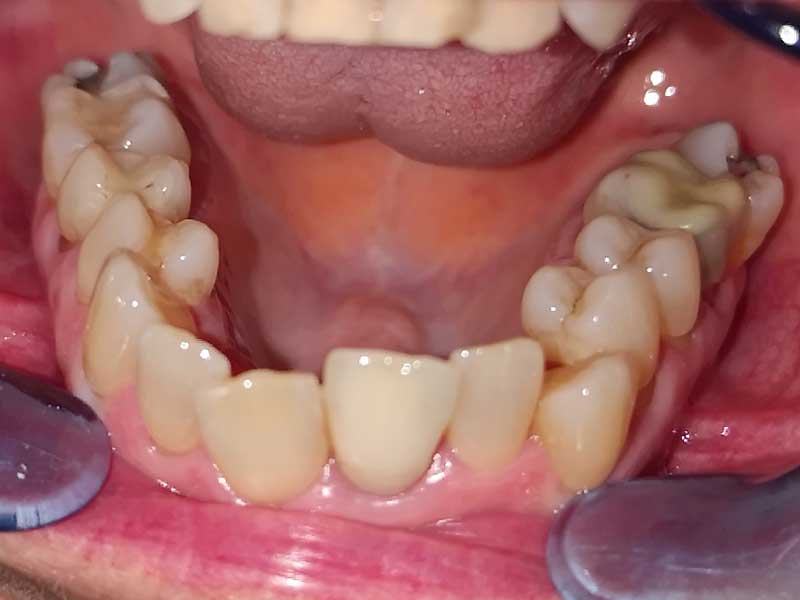

Résultat final · Juillet 2025

Après 18 mois — Une transformation complète, bi-maxillaire

La transformation est saisissante. Plus aucune bague, plus aucun fil. Les deux arcades sont alignées de façon harmonieuse.

Les deux arcades sont alignées de façon harmonieuse

L'occlusion est équilibrée et stable

Les espaces interdentaires sont cohérents sur l'ensemble des deux arcades

Les gencives sont saines — les papilles interdentaires sont présentes et bien formées

Aucune modification prothétique supplémentaire — la couleur naturelle des dents est conservée

Ce dernier point mérite attention : corriger l'alignement a directement amélioré l'hygiène, et donc la santé parodontale. L'orthodontie ici n'était pas seulement esthétique — elle était médicalement justifiée.